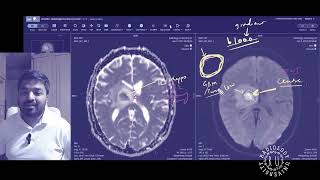

Radiology Viva Practice Case: 2 - FRCR 2B preparation